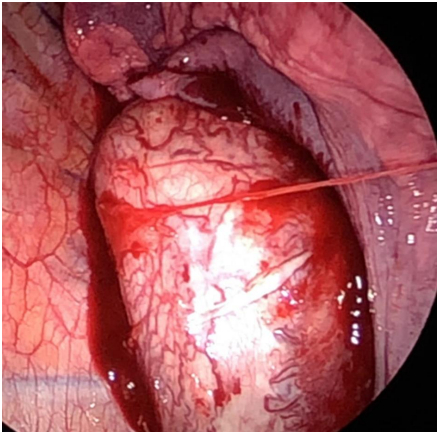

Video-Assisted Thoracoscopic Safe Minimal Invasive Surgery to Treat Posterior Mediastinal Castleman’s Tumor

Ayman Fahad Yousef, Malaz Siddeg Younis and Hajer Khaled Albalawi. 7(11): 01-06.